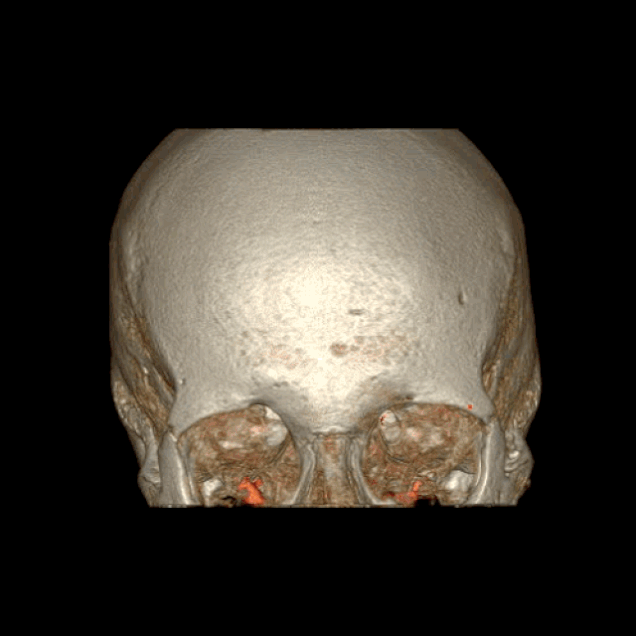

BigBrain

BigBrain es una reconstrucción digital del cerebro humano completo en 3D y ultra-alta resolución, que deja muy atrás a cualquier iniciativa anterior de este estilo. Es la herramienta esencial que necesitan los laboratorios neurológicos de todo el mundo para elucidar la forma y la función de nuestro cerebro. Y estará disponible públicamente a coste cero.

Hasta ahora existen otros atlas del cerebro, pero solo llegan al nivel macroscópico, o visible. Su resolución solo llega al nivel de un milímetro cúbico, y en ese volumen de cerebro caben fácilmente unas 1.000 neuronas. El nuevo BigBrain baja el foco hasta un nivel “casi celular”, según los científicos que lo han creado. Eso quiere decir que llega a discriminar cada pequeño circuito de neuronas que está detrás de nuestra actividad mental, y que puede abarcar toda la información disponible sobre el cerebro, desde los genes y los receptores de neurotransmisores hasta la cognición y el comportamiento.

Pese a que hay cientos de laboratorios en el mundo investigando en neurobiología, el cerebro no contaba hasta ahora con una gran planificación de este tipo, como las que se usan para secuenciar el genoma humano o encontrar el bosón de Higgs. La gran ciencia ha llegado al cerebro, y BigBrain permite por primera vez una exploración en 3D de la anatomía citoarquitectónica humana.

BigBrain, ya forma parte del dominio público, y es un gran paso hacia el entendimiento profundo del cerebro y la mente. Su objetivo no es otro que comprender los fundamentos neurobiológicos del aprendizaje y la adquisición de conocimiento, del lenguaje y las emociones, de la torpeza y de la creatividad humana. El trabajo ha sido coordinado por Katrin Amunts, del Instituto de Neurociencia y Medicina de Jülich, en Alemania; y Alan Evans del Instituto Neurológico de la Universidad McGill en Montreal, Canadá.

El cerebro de referencia se basa en el de una mujer fallecida a los 65 años, que ha sido fileteado en 7.400 secciones histológicas de solo 20 micras (el espesor de un cabello, y cerca de la dimensión de una célula). El BigBrain, según sus creadores, abre el camino para entender las bases neurobiológicas de la cognición, el lenguaje y las emociones, y también para investigar las enfermedades neurológicas y desarrollar fármacos contra ellas.[3]